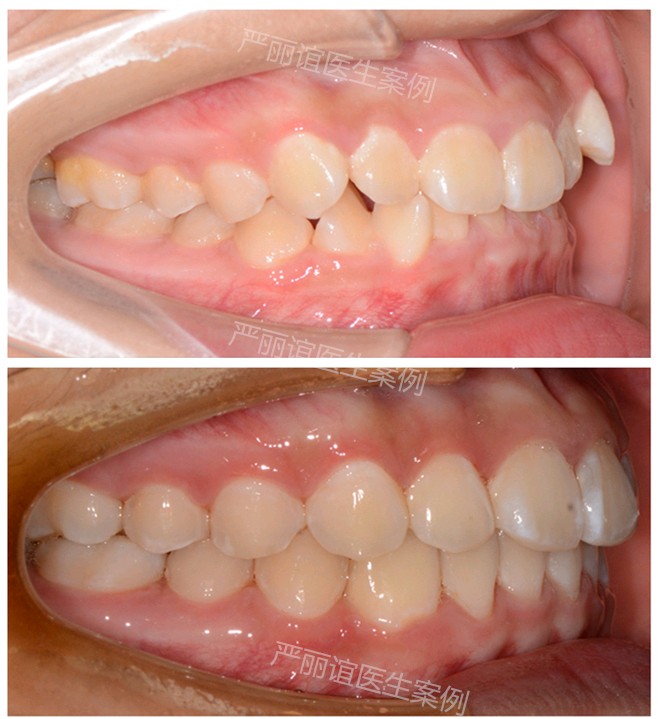

这个患者上颌两个小虎牙外凸,下颌一个畸形过大牙,自觉很影响颜值,想通过矫正改善。

检查发现她上颌最后还有一定的骨量,加上两个小虎牙外凸不是特别严重,需要2-3mm就可以排齐。下颌的畸形过大牙外面的保护层比其他牙齿厚,沟通后选择了上颌推磨牙远移,下颌片切的矫治方案。

一年半时间,矫正结束前后对比图如下。